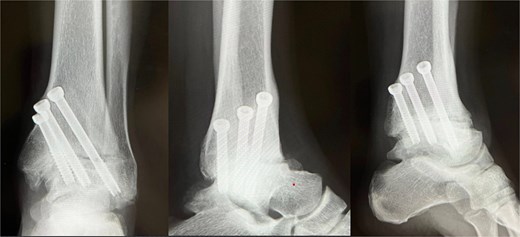

Under arthroscopic visualization, inflamed synovial tissue and degenerated cartilage were removed until healthy subchondral bone was exposed. The tibiotalar joint was anatomically reduced and fixed in neutral alignment with axial compression using three 6.5-mm cannulated cancellous screws inserted from the medial malleolus (Fig. 3).

Immediate postoperative radiograph (X-ray). Ankle arthrodesis using three 6.5-mm cannulated cancellous screws (CCS).